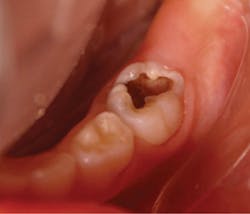

There are important considerations that are necessary when SDF application may be recommended. We consider SDF application to be a restorative dentistry procedure, as active caries is treated and the treatment is not reversible. The procedure code for applying SDF is D1354 as interim caries arresting medicament application. Reimbursement for this procedure varies among states and insurance companies. Most importantly, SDF provides a less invasive and an inexpensive approach for managing caries. However, SDF is not a prevention measure and cannot replace the use of fluoride varnish in preventing caries.The main disadvantage of SDF is the permanent discoloration of the enamel and dentin of the lesion. If SDF is in contact with skin, it creates temporary staining and will disappear in two to 14 days after natural exfoliation of the skin.14 SDF will darken tooth structure, so it is very important that parents understand this fact. The American Academy of Pediatric Dentistry recommends that informed consent be obtained from parents prior to SDF application.13,15 The saying “a picture is worth a thousand words” seems appropriate in these circumstances, where SDF will turn infected tooth structure black (figures 1 and 2). Be sure parents and caregivers are well aware of the staining associated with SDF. Additionally, SDF can also permanently stain clinical operatory surfaces and clothes.

• Remove gross debris from the cavitation. Excavation of dentinal caries is not necessary (figure 1).